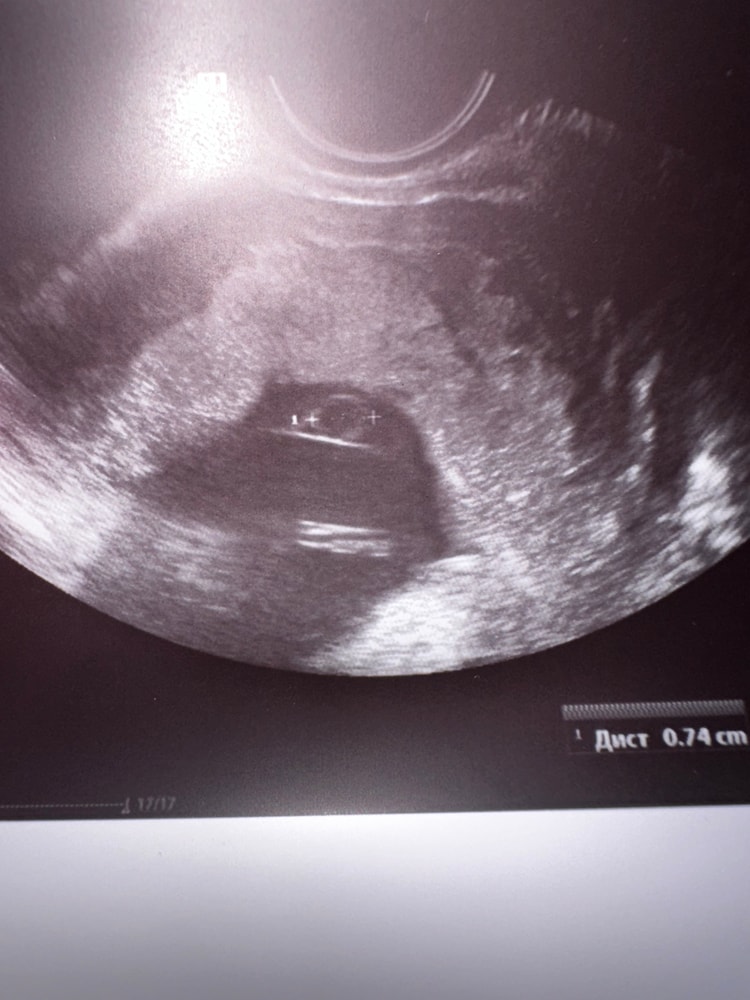

Aurelia Man ,

Вот как она намерила, даже так видно, что это не внутренний диаметр жм